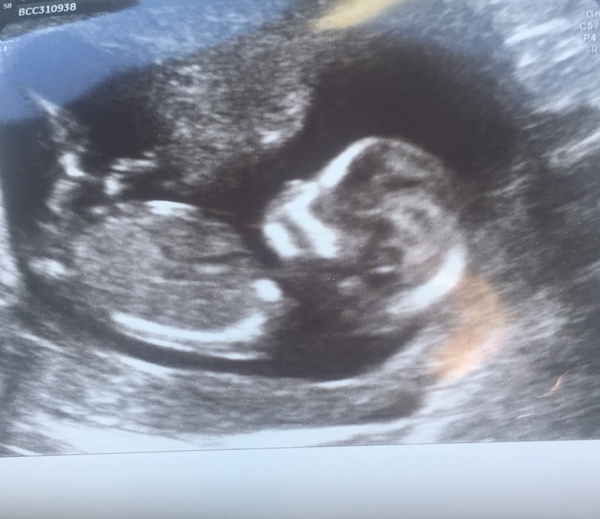

Baby very bouncy. Would not lie still for crown to rump measurement so they measured head in the end. 13 weeks 4 days so gained another day.